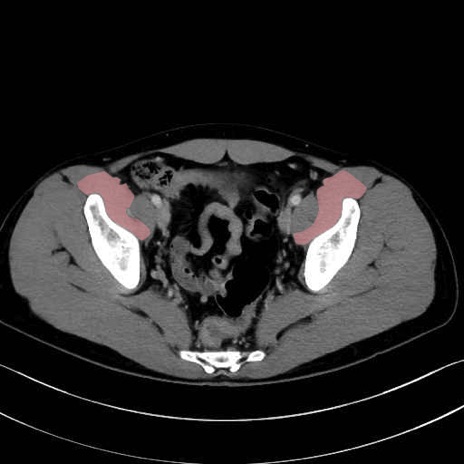

腸骨筋 (Iliacus)